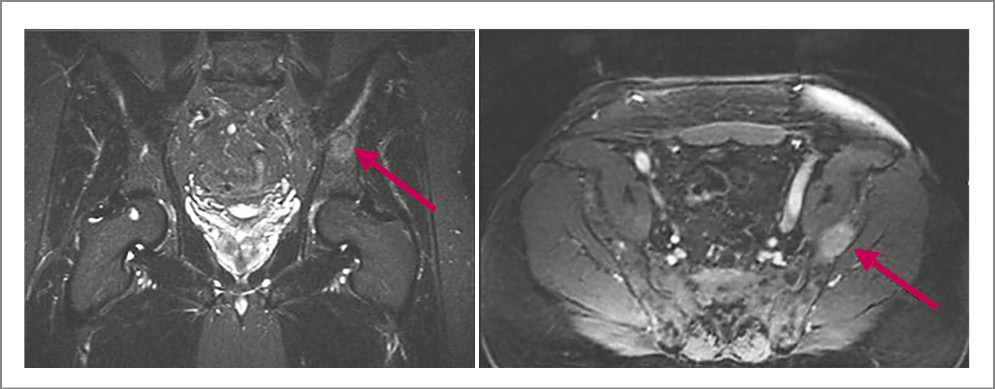

По данным магнитно-резонансной томографии (МРТ) ГМ с контрастированием в островковой доле справа с распространением на лобную и височную визуализируется внутримозговое кистозно-солидное образование с бугристым контуром размером 3,7×3,3×2,9 см. Отмечаются выраженный перифокальный отек с переходом на лобную и височную доли, базальные ядра со смещением срединных структур на 1,3 см. Аналогичные образования выявлены в задних отделах левой височной доли и левом полушарии мозжечка, размеры которых составили 1,1×0,8 и 0,5×0,6 см соответственно. В гипофизе определяется кровоизлияние. Соответственно, у больного имеются объемные образования в правой островковой, левой височной долях и левом полушарии мозжечка с кровоизлиянием в гипофиз (рис. 1, 2).

По данным МРТ органов малого таза с контрастированием установлено, что предстательная железа не увеличена – 3,1×4,4×4,0 см. В периферической и транзиторной зонах правой доли на уровне верхушки и среднего сектора имеется зона пониженного сигнала – 2,2×1,0×1,7 см – с ранним накоплением контраста. Распространения за пределы капсулы нет. Парааортальные и забрюшинные лимфоузлы не увеличены. Магнитно-резонансная картина соответствует 5-й категории изменений по шкале PI-RADS (PI-RADS 5) – очень высокий риск (наличие клинически значимого рака крайне вероятно); рис. 3.

Рис. 3. Больной Л., 66 лет. МРТ органов малого таза. Образование в правых отделах периферической зоны предстательной железы без признаков распространения за пределы органа размером 2,2×1,0×2,7 см (стрелки). PI-RADS 5.

В левой подвздошной кости выявлено объемное образование размером 2,4×1,3 см метастатического характера, накапливающее контраст (рис. 4).

Рис. 4. Больной Л., 66 лет. МРТ органов малого таза. Контрастпозитивное образование вторичного характера в левой подвздошной кости (стрелки).